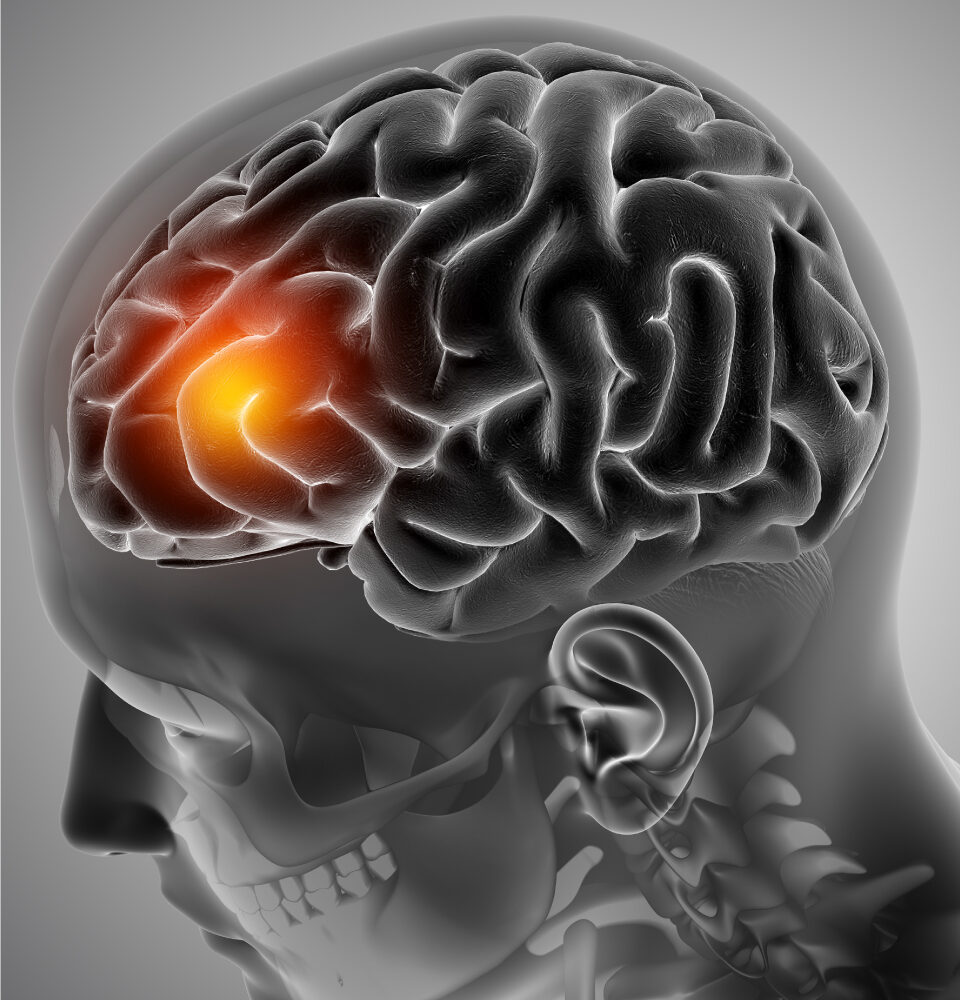

The images or names of people used in the articles are for representation purposes only and do not relate to any individual who is dead or alive. The photos and illustrations used in the magazine are sourced from authorized sources that cover relevant copyright. Copying or re-using any content from this magazine is strictly prohibited.